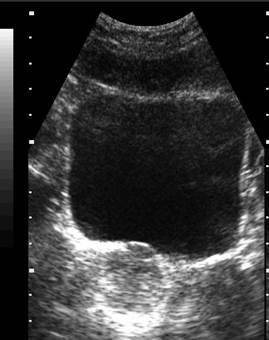

| Рис. 6.28. Экскреторная урография. Резкое расширение и деформация чашечек в правой почке. Гидронефроз правой почки. |